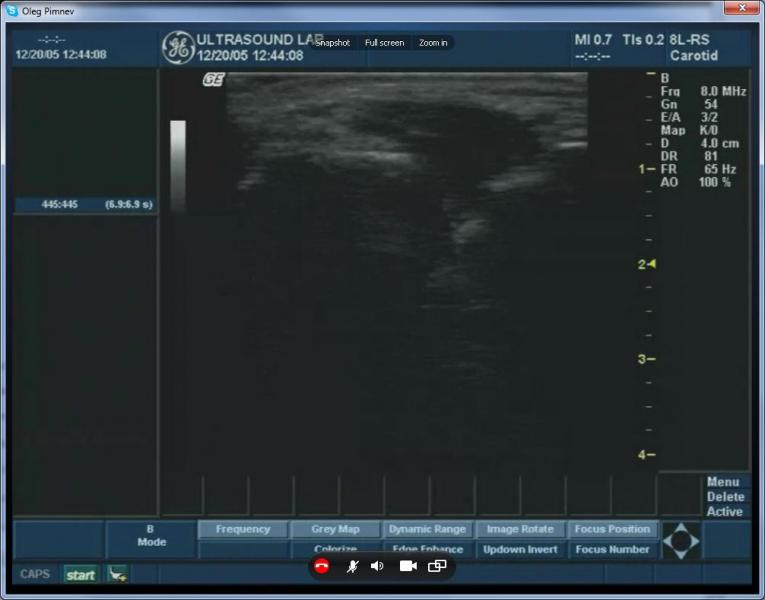

以下截圖是來自Skype超聲波圖像的廣播視頻:

在這個(gè)屏幕截圖、視頻從一個(gè)GE Logiq

Book在網(wǎng)絡(luò)實(shí)時(shí)廣播到遠(yuǎn)程參與者。

在上面的截圖中,

由于Skype視頻壓縮可以看到典型的色塊發(fā)生。不幸的是,因?yàn)镾kype沒有視頻質(zhì)量控制的選擇,沒有辦法擺脫他們。